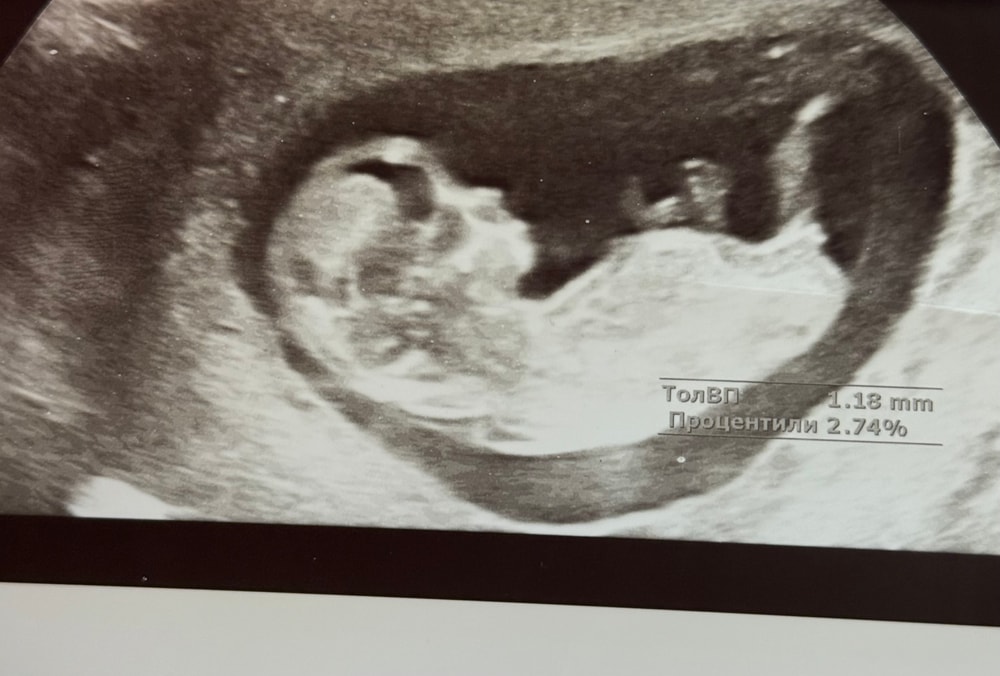

по бугорку на кого похож?

Пол малышаДевочки на кого пол похож?у кого был бугорок такой ?? и какой был пол)

Катя, чуть приподнят , сомнительно , ровно в 12 недель скрининг делала